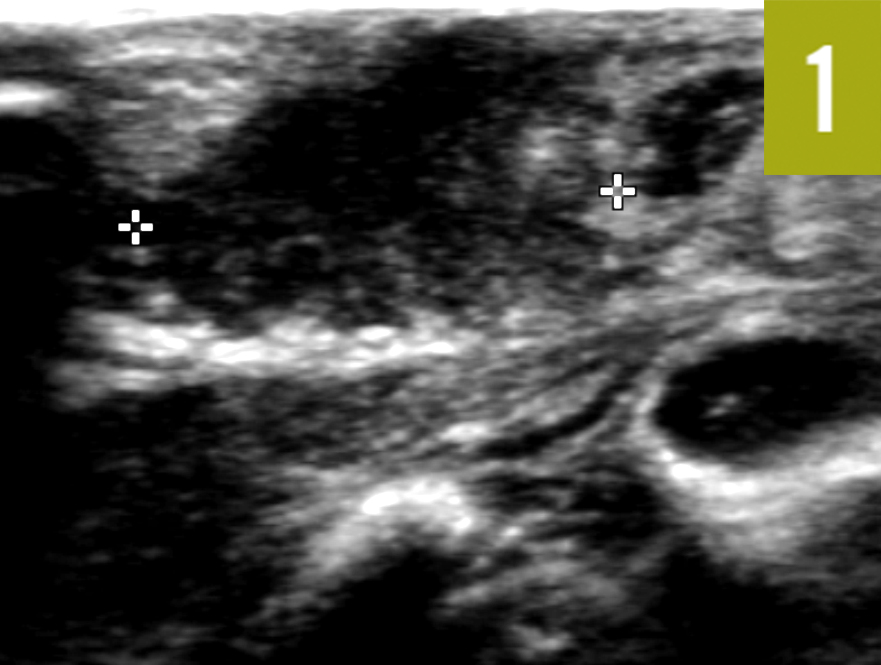

Granulomatous Lobular Mastitis Imaging, Diagnosis, and Treatment AJR